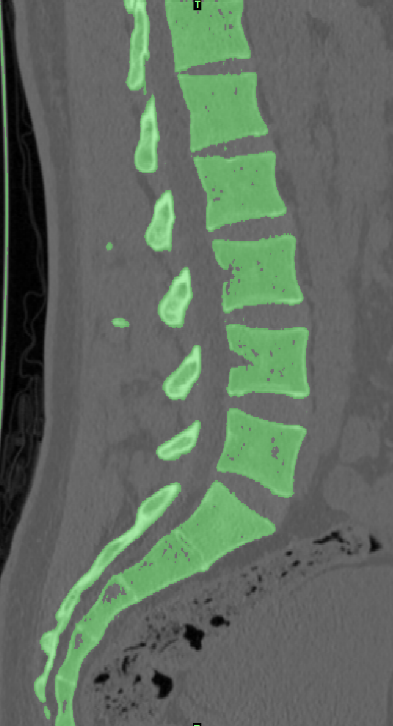

选取一名27岁青年男性志愿者在我院行腰椎螺旋CT扫描,扫描平面为:第十二胸椎椎体至尾椎末端,扫描厚度为0.625mm,得到二维断层CT图像489张,以DICOM格式进行储存,导入计算机服务器。使用Mimics 19.0图像生成和编辑处理软件,直接读取 DICOM格式的CT扫描数据进行三维重建,见图 10。根据软件中不同的灰度值来区分不同的组织,用 Mimics 软件的阈值分割及区域增长功能画出腰椎(L3-5),不同的锥体用不同的颜色区分,最后用图像填充功能填补图像中的空洞,接着进行不同部位的三维重建,得到仅包含骨性结构(L3-5)的模型。将Mimics 软件得到的模型以STL格式模型文件导入Geomagic wrap2017软件中,抹去模型钉状物和多余特征,然后对模型进行优化光滑处理,将L3-5光滑处理后的每个锥体进行复制,再将光滑后的模型在精确曲面中进行网格划分,并进行构建曲面片及修理曲面片,最后合成三维实体模型,见图11。此时将复制的每个椎体模型外层向部件内部偏移2mm,内部充当松质骨,外部的则定义为皮质骨,椎弓根后部统一由皮质骨组成。随后将模型以STEP格式文件导入Solidworks2020软件中生成L3-5的实体模型零件,并在模型零件中构建椎间盘、髓核、上下终板和软骨,完成的实体模型,此时的模型为单纯的正常腰椎三维几何模型,各结构并未赋予材料属性与网格划分,见图12。将模型导入ANSYS软件中,随后对模型中皮质骨、松质骨、软骨、终板、纤维环、髓核赋予相应的材料属性赋值,尽可能地还原各组织材料的生理状况,提高模型的可靠性。定义关节突关节面为 Frictional,摩擦系数设为0.1。在connections中建立spring模块,模拟前纵韧带、后纵韧带、黄韧带、棘间韧带、棘后韧带、横突间韧带及关节囊韧带,各韧带对应刚度赋值。建立完成后,对模型进行mesh操作构建网格,见图13。